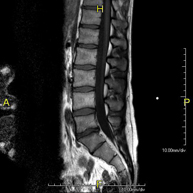

Prueba diagnóstica no invasiva que consiste en la obtención de imágenes de alta definición anatómica de la lumbar y sacra mediante el empleo de un campo electromagnético y ondas de radio (con un emisor y un receptor). No utiliza radiación ionizante. Indicaciones: traumatismos, ciática, hernias discales, tumores, infecciones. - RM Sacro-cóccix

Prova diagnòstica no invasiva que consisteix en l'obtenció d'imatges d'alta definició anatòmica de la columna lumbar i sacre mitjançant l'ús d'un camp electromagnètic i ones de ràdio (amb un emissor i un receptor). No utilitza radiació ionitzant. Indicacions: traumatismes, ciàtica, hèrnies discals, tumors, infeccions - RM Mielografia